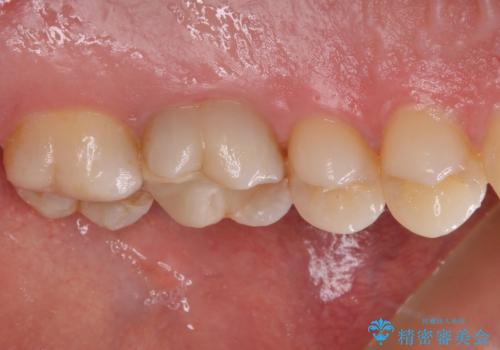

レントゲン的には根管治療の治癒経過良好で、手術後に症状や違和感がなくなり、無事セラミッククラウンを装着することができました。